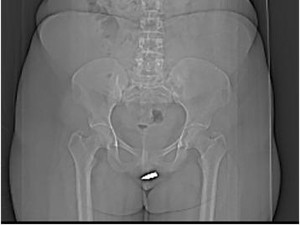

Melihat hal yang dialaminya, wanita 24 tahun itu pergi ke Rumah Sakit Erdoğan di Mogadishu. Di sana, dokter memastikan bahwa peluru yang berukuran dua sentimeter itu bersarang di klitorisnya.

Salah satu cara untuk mengeluarkannya adalah dengan menjalani operasi. Dari hasil CT Scan, peluru itu terlihat jelas dan dapat terasa saat disentuh langsung oleh petugas medis.